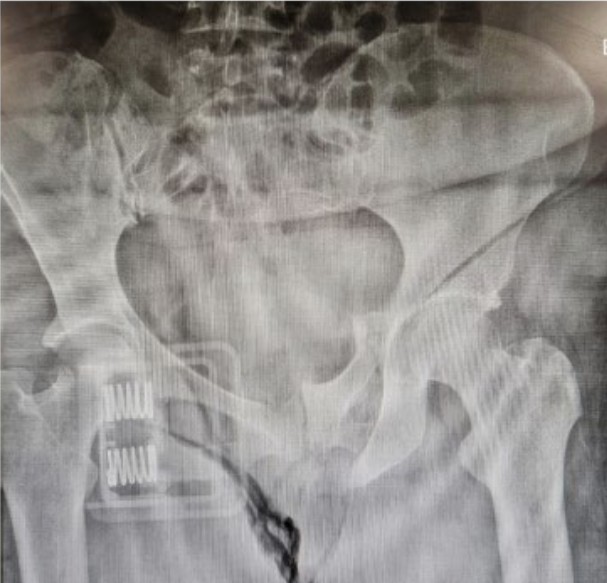

Pelvic injury

A 37-year-old woman presents following a high speed MVA. Her GCS is 15.